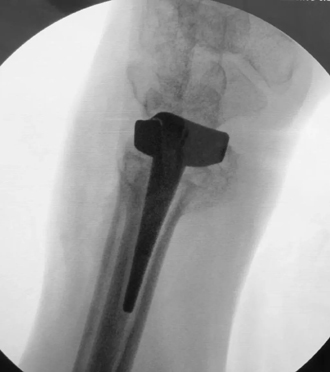

假体置入后术中透视图

历经3个多小时的手术,患者的桡骨远端被全新的人工假体所代替。同时因采用机器人辅助精准定位,假体摆放位置非常满意,完全实现术前模拟情况。相信经过一段时间的康复锻炼,患者一定能够获得满意结果。